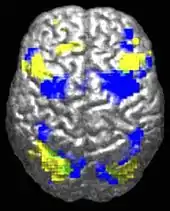

The underconnectivity theory of autism hypothesizes that autism is marked by underfunctioning high-level neural connections and synchronization, along with an excess of low-level processes.[41] Evidence for this theory has been found in functional neuroimaging studies on autistic individuals[42] and by a brainwave study that suggested that adults with ASD have local overconnectivity in the cortex and weak functional connections between the frontal lobe and the rest of the cortex.[43] Other evidence suggests the underconnectivity is mainly within each hemisphere of the cortex and that autism is a disorder of the association cortex.[44]

Functional connectivity studies have found both hypo- and hyper-connectivity in brains of people with autism. Hypo-connectivity seems to dominate, especially for interhemispheric and cortico-cortical functional connectivity.[48]